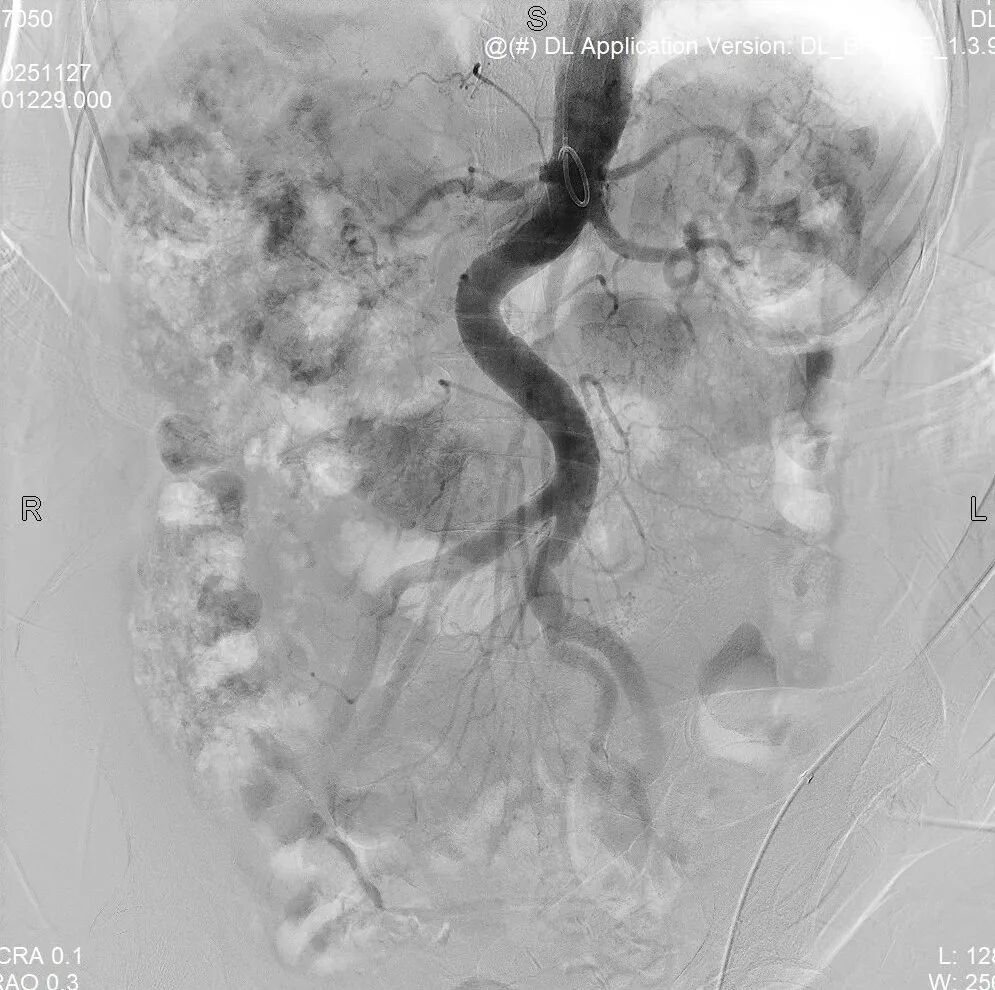

外院造影:

右肾动脉重度狭窄

2.导管配合0.035导丝进入腹主动脉下端,造影示:腹主动脉走形迂曲,血流通畅,右肾动脉主干起始段重度狭窄>90%,远端及分支显影浅淡。